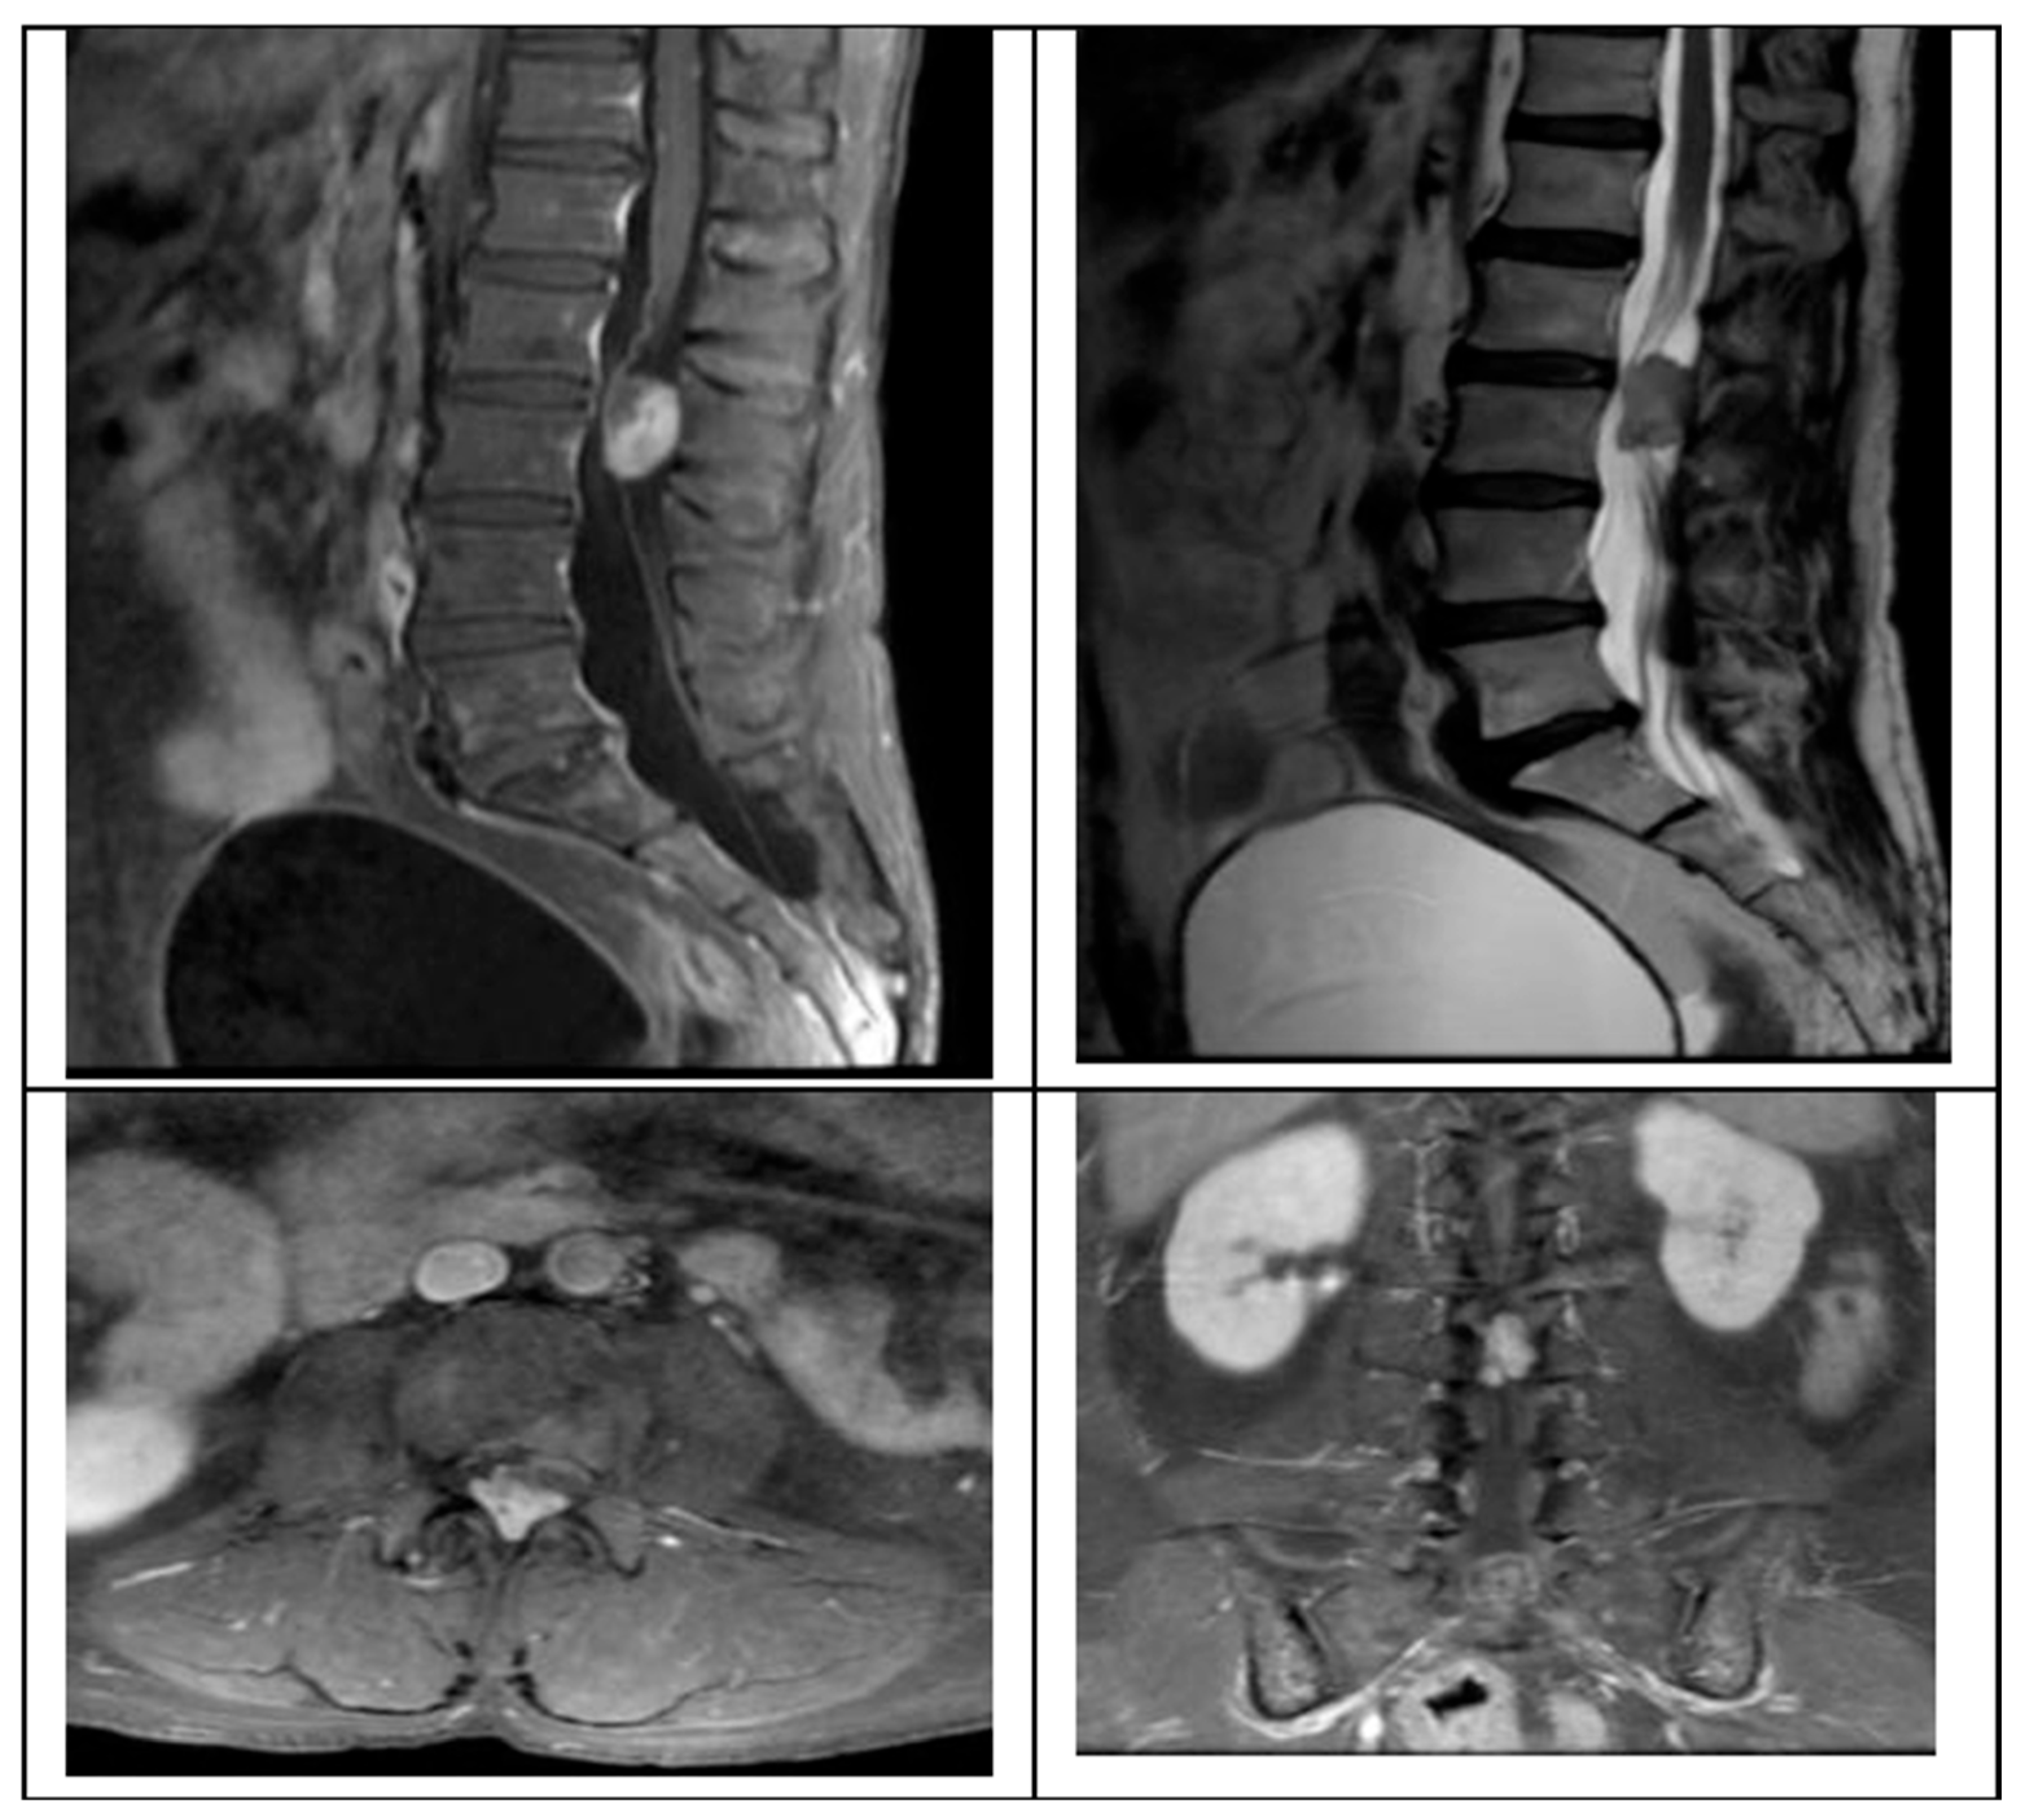

3.5. Illustrative Case

Schwannoma

We present the case of a 58-year-old female presenting with a 2-month history of progressive left leg radiculopathy (Leg VAS 9/10), low back pain (Back VAS 7/10), and weakness in both lower limbs resulting in an inability to ambulate, along with neurogenic bladder. MRI revealed an L2–L3 intradural extramedullary lesion occupying 80% of the spinal canal (

Figure 1).